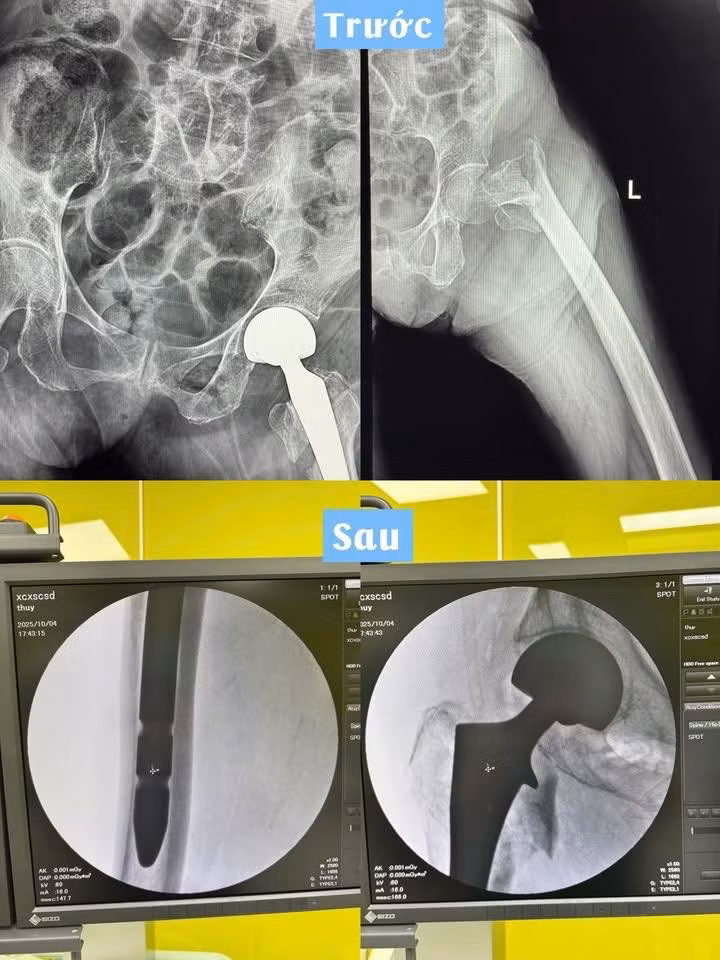

thay-khop-hang-2.jpg

Hình ảnh xương đùi của bệnh nhân trước và sau phẫu thuật - Ảnh BVCC

Các bác sĩ phân tích, vị trí đầu trên xương đùi tiếp giáp với xương chậu bằng khớp háng được gọi là vùng cổ xương đùi. Cấu trúc vùng cổ xương đùi tương đối đặc biệt, chúng được tạo nên bởi hai hệ thống bè xương riêng biệt là hệ thống bè xương hình vòm và hệ thống bè xương hình quạt. Vị trí giữa hai hệ thống này là vị trí gãy thường gặp ở vùng cổ xương đùi, nên được gọi là điểm yếu của cổ xương đùi – tam giác Ward.

Dưới tác động của một lực đủ lớn để gây ra đường gãy tại điểm yếu này thì ổ gãy có xu hướng đi theo các bè xương dẫn đến gãy liên mấu chuyển hoặc gãy cổ xương đùi.

Sự khác nhau giữa gãy liên mấu chuyển và gãy cổ xương đùi ở chỗ gãy liên mấu chuyển là tình trạng gãy ngoài bao khớp, vị trí vùng liên mấu chuyển giàu mạch máu nuôi dưỡng hơn nên quá trình liền xương cũng xảy ra nhanh hơn và ít gây biến chứng hoại tử chỏm hơn so với gãy xương đùi.